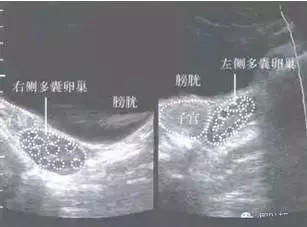

我们来一张超声底下真实版本:

多囊卵巢综合征声像(经腹扫查)示意图